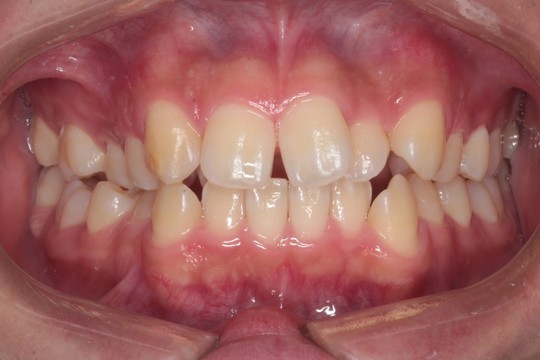

『交叉咬合(こうさこうごう)』は

上下の歯の関係が一部反対になっている状態の歯並びです

クロスバイトとも呼ばれます 今回は右の5番目あたり(向かって左側)に起きています

『叢生(そうせい)』は

草むらを表す『叢(そう)』のように込み入った歯並びを指します

日本人に多い、前歯がデコボコした歯並びです

交叉咬合と重度叢生を非抜歯のインビザラインで治療しました